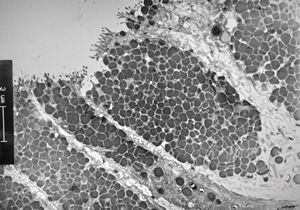

normal mucosa - stomach